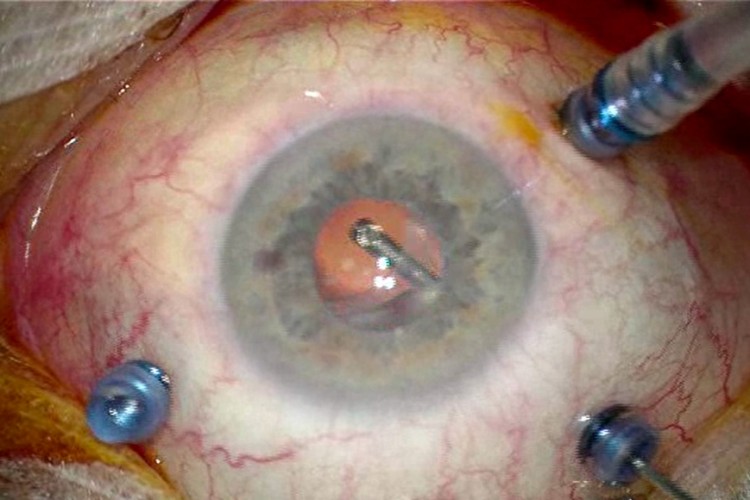

Greffe cornée Carlevale